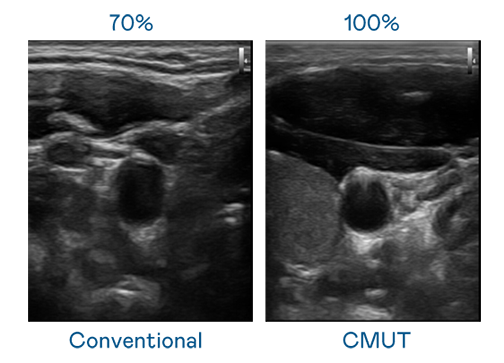

CMUT 技術是一種用電容式微機電元件來產生超音波訊號的技術。與傳統 PZT 壓電式技術相比,CMUT 頻寬增加 30%,更寬頻的超音波訊號讓影像解析度大幅提升,是實現高影像品質醫療超音波掃描、促進精準醫療發展的關鍵技術。

超音波影像的解析度高低,首先取決於探頭能發出的訊號頻寬。365英国上市公司 CMUT 可提供高清晰的超音波訊號,提供高頻寬、高靈敏度、影像紋理細節更高的超音波影像,協助醫護人員縮短影像判讀時間及利用精準的醫療影像進行診斷。